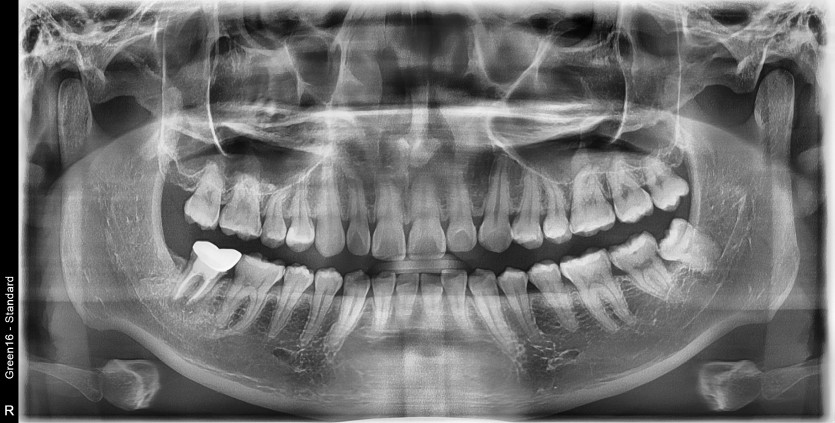

#28,38 사랑니 발치

구강외과 전문의가 당일 발치했습니다.